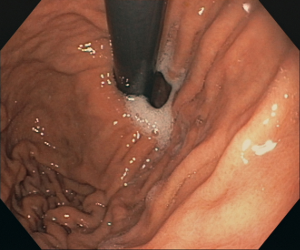

Conventional white-light endoscopy has a relatively low sensitivity, low specificity and high inter-observer variability for the diagnosis of atrophic gastritis. Thus, it is thought to be insufficient to reliably diagnose it. Our goal is to improve endoscopic accuracy for the diagnosis of atrophic gastritis using deep learning.

Our convolutional neural network was trained to analyze endoscopic images from the proximal stomach, achieving an accuracy of 92.9% and performing significantly better than the combined results of 6 independent endoscopists. With this web tool we want to provide wide access to this software. It allows you to upload your own endoscopic images for analysis, and provides an indicative diagnosis.